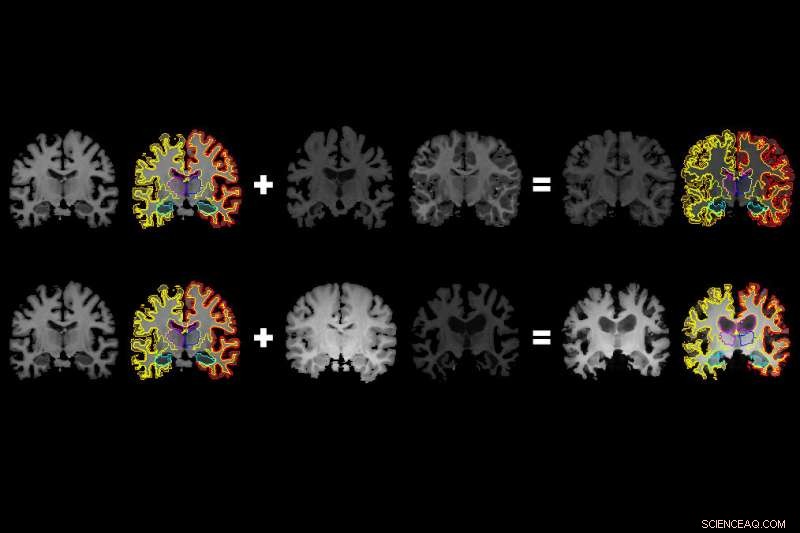

MIT researchers have developed a system that gleans far more labeled training data from unlabeled data, which could help machine-learning models better detect structural patterns in brain scans associated with neurological diseases. The system learns structural and appearance variations in unlabeled scans, and uses that information to shape and mold one labeled scan into thousands of new, distinct labeled scans. Credit: Amy Zhao/MIT

In generating a new scan, the system applies a random flow field to the original labeled scan, which shifts around voxels until it structurally matches a real, unlabeled scan. Then, it overlays a random intensity transformation. Finally, the system maps the labels to the new structures, by following how the voxels moved in the flow field. In the end, the synthesized scans closely resemble the real, unlabeled scans—but with accurate labels.